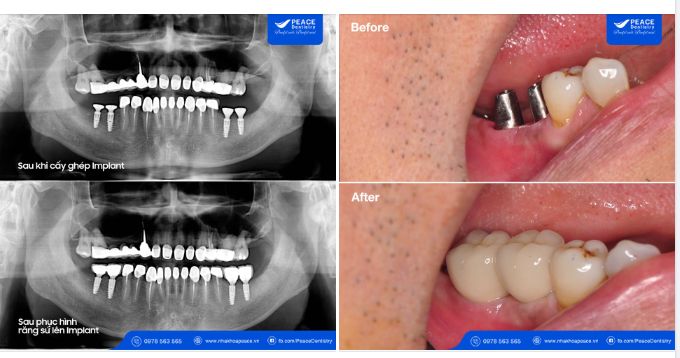

A: Trồng răng Implant sẽ bao gồm 2 giai đoạn là: cấy ghép trụ Implant và phục hình trên Implant (cố định abutment và mão sứ). Tùy vào mỗi trường hợp mà giai đoạn 1 và giai đoạn 2 sẽ cách nhau từ 1 tuần, 1 tháng, 2 tháng, 3 tháng... Cụ thể có thể chia thành 2 trường hợp:

: Phục hình trên Implant (cố định Abutment và mão sứ) sau khi cấy ghép Implant chỉ 1 tuần. Đây còn gọi là cấy ghép Implant phục hình tức thì. Trường hợp này thường chỉ định cho 2 trường hợp: xương tại vị trí cấy ghép Implant dày và đủ khả năng chịu lực tức thì, hoặc các trường hợp làm toàn hàm All-on-4 Implant.

: Phải chờ từ 1 - 6 tháng sau khi cấy ghép Implant mới phục hình trên Implant. Tức là sau khi cấy ghép trụ Implant, khách hàng phải chờ đợi từ 1 - 6 tháng sau mới có thể tiến hành gắn Abutment và mão sứ lên Implant. Đây cũng là trường hợp phổ biến hơn.

Căn cứ để xác định phải chờ bao lâu sau khi cấy trụ Implant mới có thể cố định răng sứ sẽ dựa vào film Cone Beam CT được chụp lúc thăm khám, bác sĩ chuyên khoa sẽ báo chính xác với bạn.